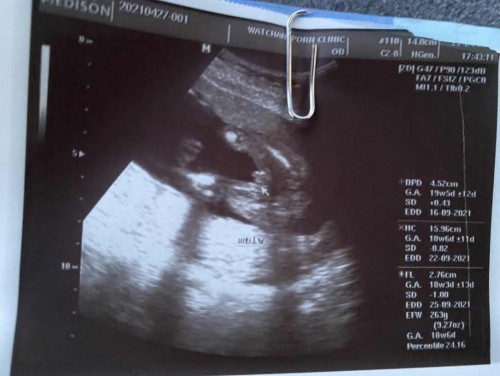

น่าจะผู้ชายนะค่ะ อันนี้ของที่บ้านค่ะ ชัดเจนมากค่ะ

ผู้ชายชัวร์ค่ะ ซาวน์มาท่าเดียวกันเลยค่ะ

ชาย ค่ะ..เหมือนแอบเห็นจู๋นิดๆ

จู๋โพล่ชัดมาก ชายค่ะ

เราว่าเราเห็น ปิกาจู🤣🤣